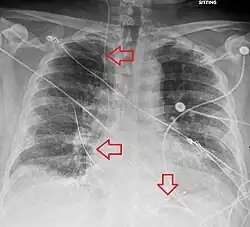

Pós-procedimento

Uma radiografia após o procedimento é obtida para confirmar a colocação do eletrodo de estimulação e descartar complicações como pneumotórax [2][3]. A desfibrilação e a cardioversão ainda podem ser realizadas em alguém com marcapasso temporário[2].

As complicações incluem disritmias cardíacas e aquelas relacioniadas à colocação de um cateter venoso central, como o pneumotórax [3].